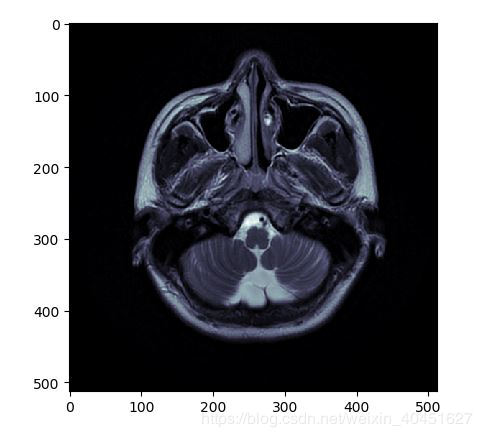

借助 Matplotlib (Pydicom官方文档中使用的方法)

from matplotlib import pyplot

pyplot.imshow(ds.pixel_array,cmap=pyplot.cm.bone)

pyplot.show()效果如图所示:

但真实的图像是:

显然颜色是有区别的.导致这种差别的原因是pyplot函数使用的cm也就是"color map" 是简单的"bone" 并不能满足医学图像的要求.